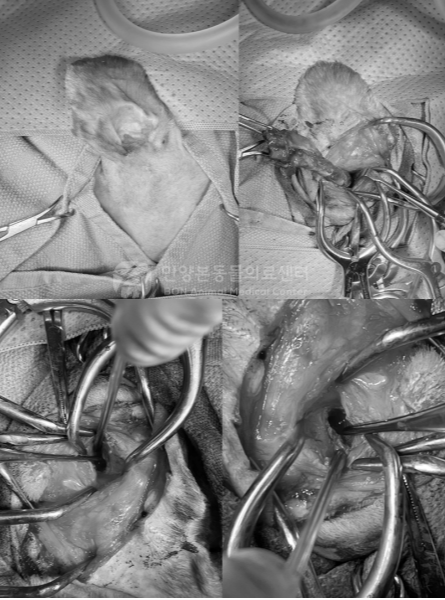

이번 환자에서는 수술이 어떻게 진행되었나요?

수술 중 확인된 주요 소견은 다음과 같았습니다.

• · 외이도 전반적인 벽 비후

• · 외이도 석회화

• · 중이 내부 다량의 삼출액

중이 내부에 있던 삼출액은 세균 배양 및 항생제 감수성 검사를 위해 채취했고 이후 중이 내부를 여러 차례 세척한 뒤 수술을 마무리했습니다.

이번 수술은 단순히 겉귀만 제거한 것이 아니라 중이 안쪽의 염증성 물질과 감염 요인을 함께 정리하는 과정이 포함된 치료였습니다.

강아지 외이염 수술, TECA-LBO 수술, 전이외도적출술 및 외측고포절제술 장면

[TECA-LBO 수술]